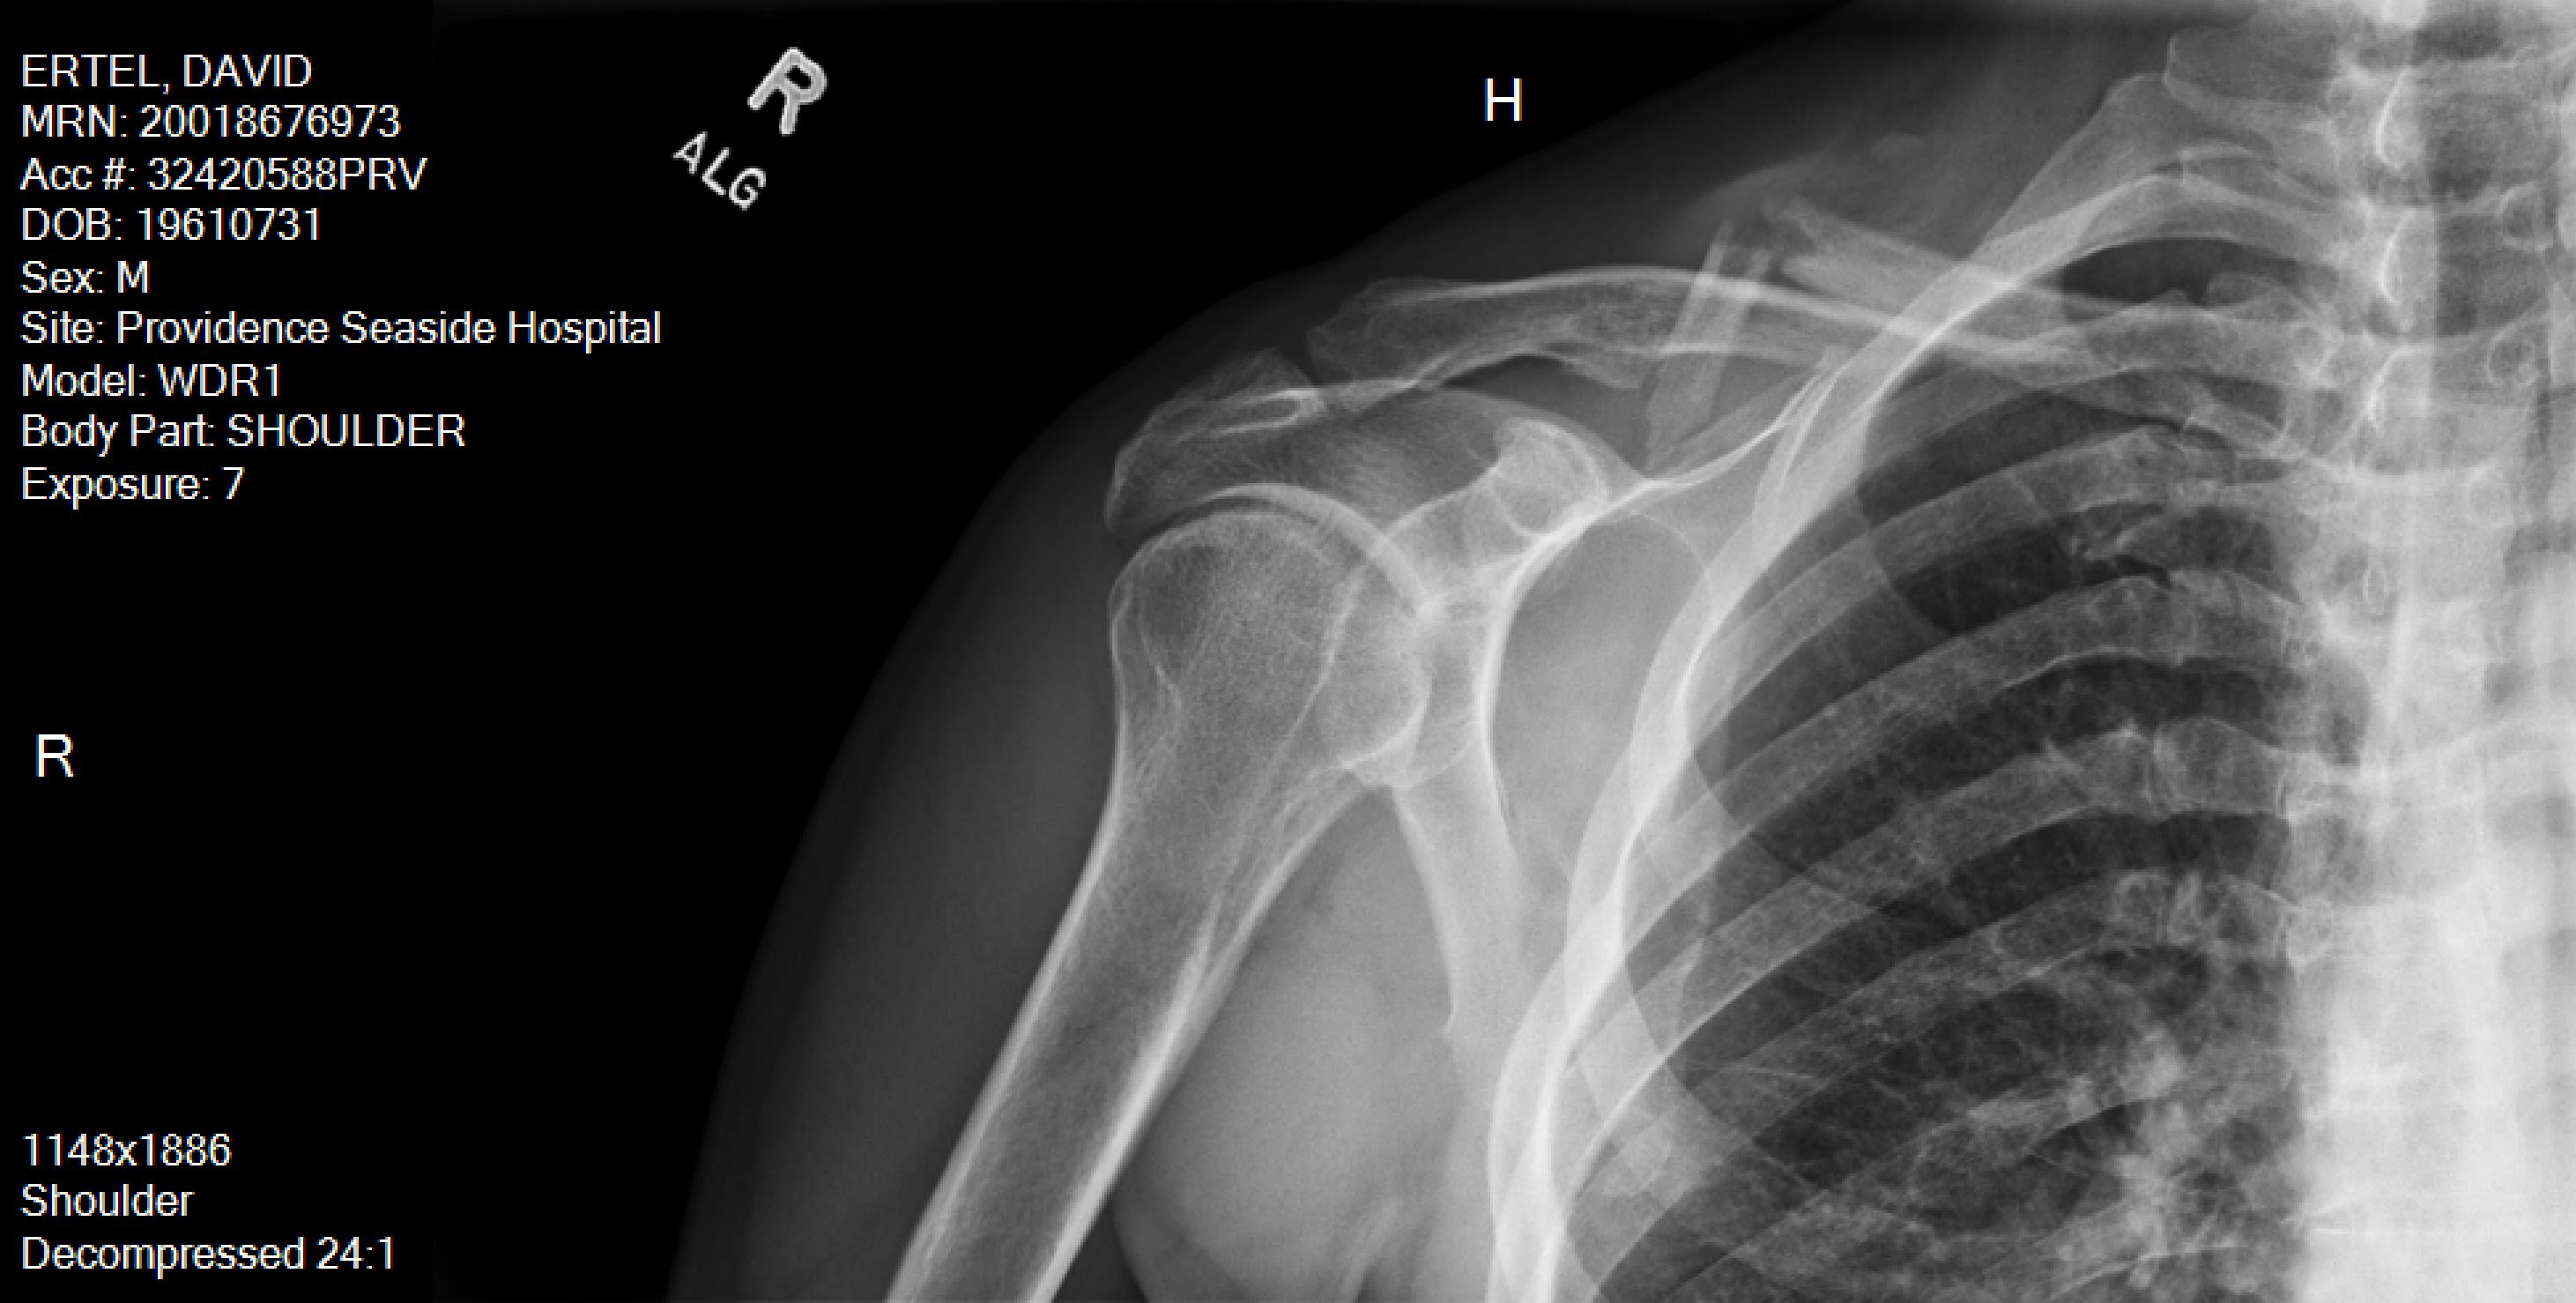

At the hospital, they confirmed the break. It was Sunday so they couldn’t do much more. They sent me home with some drugs and a sling. I had a follow-up meeting with an orthopaedic surgeon on Wednesday and then surgery on Thursday. These days they only insert plates in collarbones that have compound breaks. Mine was a “z” compound fracture – not good – I needed a plate. Without surgery, one of my arms would have been about an inch shorter than the other, easy call, get the surgery. Post operation, I now have a plate and 8 screws in my collarbone. For the record Nancy has a plate and 11 screws in her collarbone so she must have broken hers worse than I did.